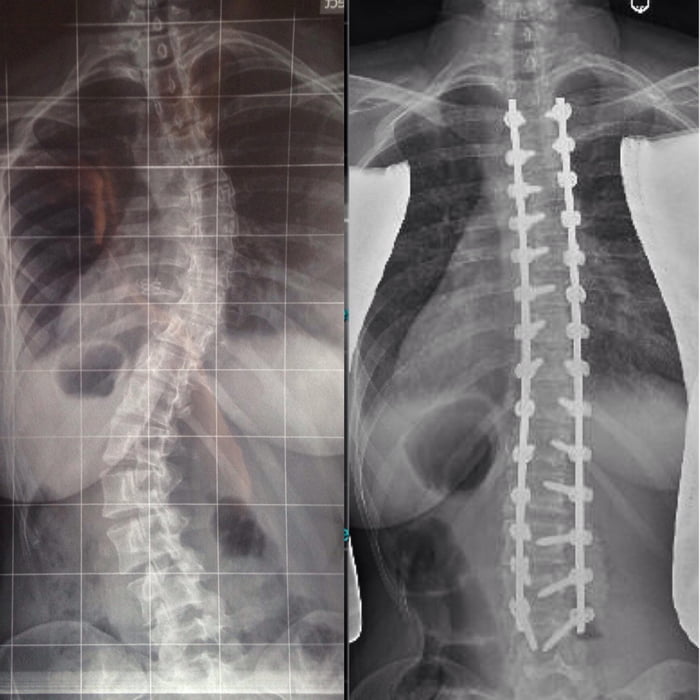

Искривление позвоночника: причины и последствия на снимках

Раздел: Визуальный дайджест